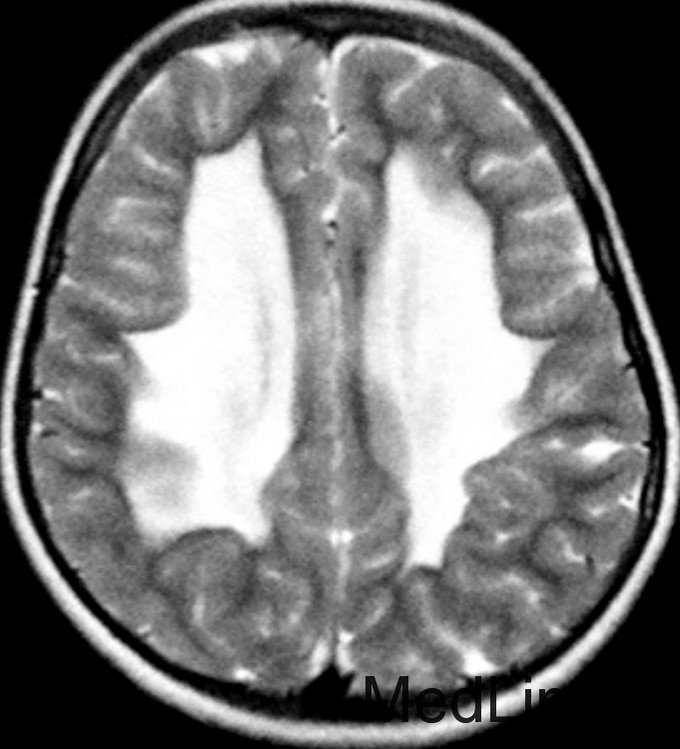

神经科查体显示肌僵直,腱反射亢进,双侧病理征阳性,轻度的小脑共济失调,振动觉及本体觉异常。CSF正常。 T2WI显示幕上及幕下白质T2高信号。内囊后肢、脑干皮质脊髓束、小脑中脚均受累。脊髓T2WI可见皮质脊髓侧束T2高信号。